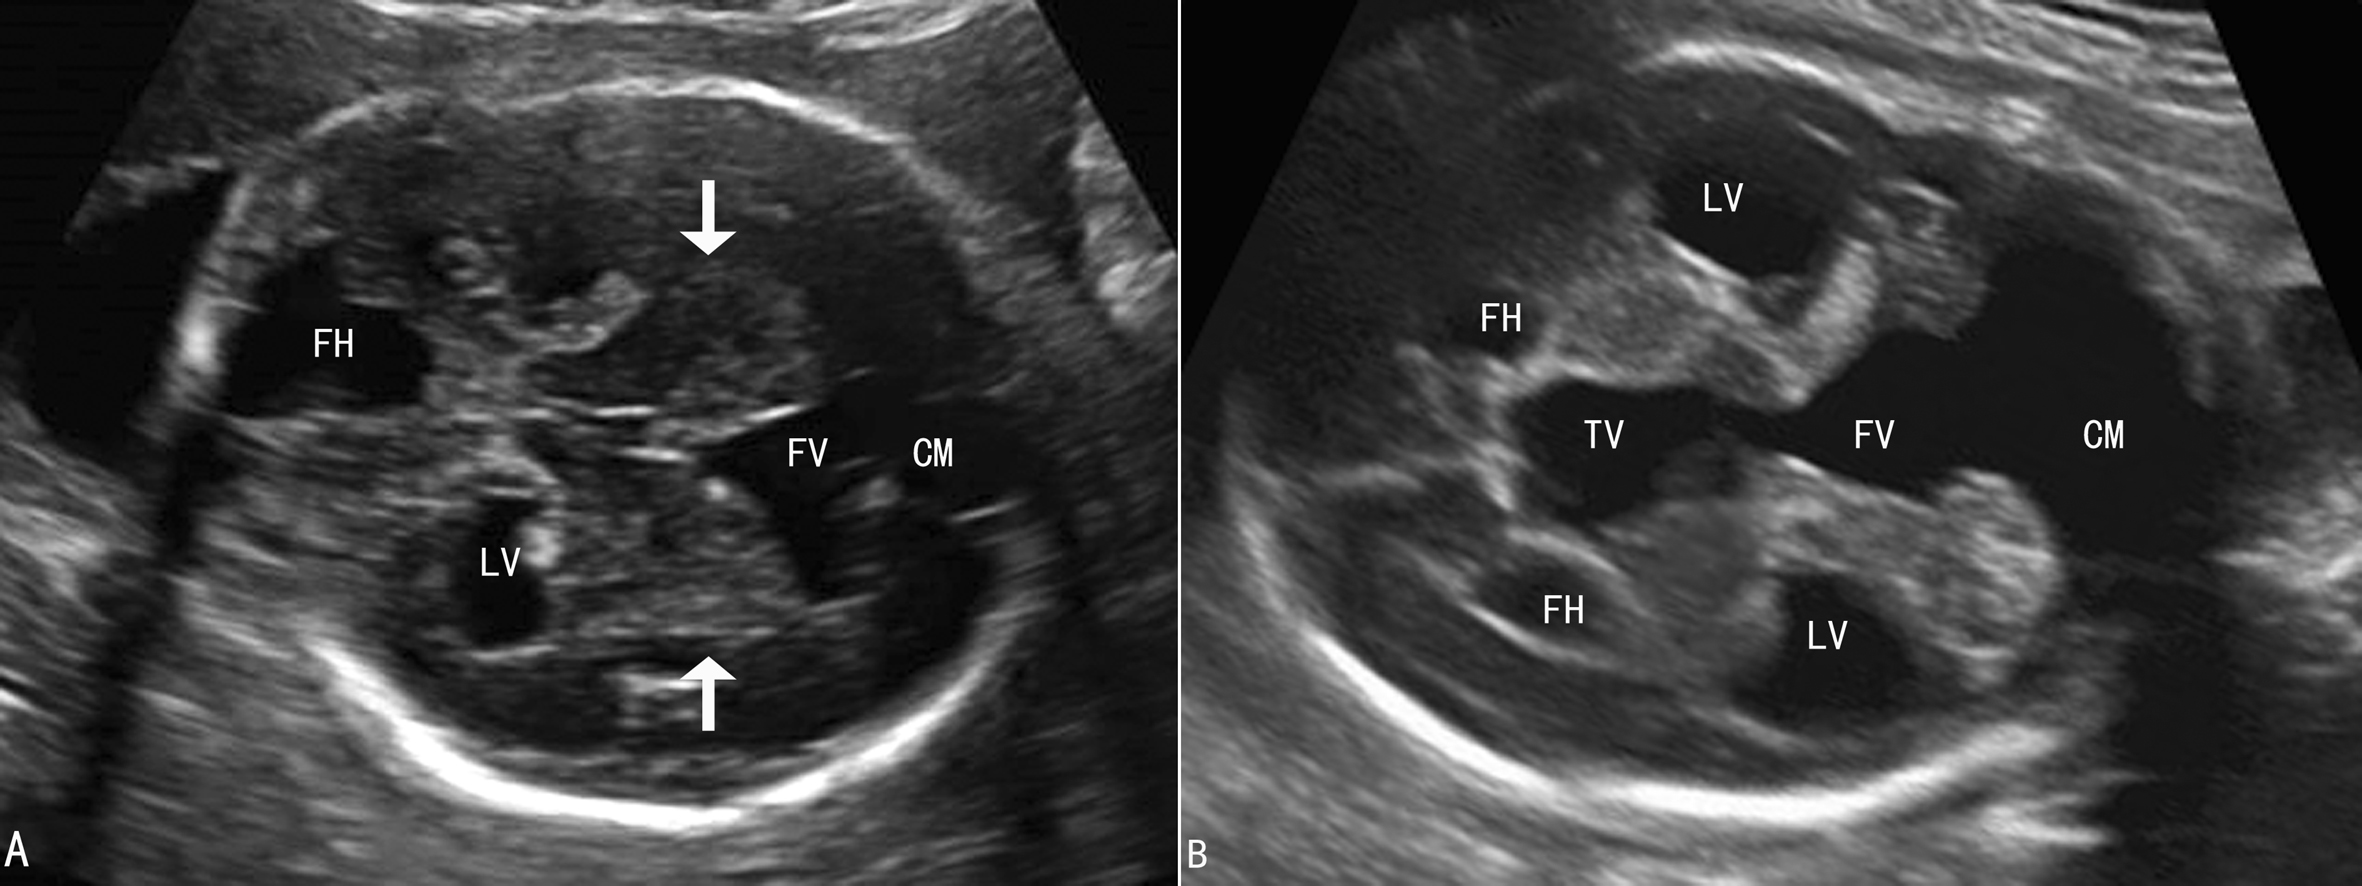

1.DWM 典型DWM表现为小脑蚓部完全缺失,两侧小脑半球向两侧分开,第四脑室与后颅窝池相通,后颅窝池明显扩大(图18-29A)。产前有些合并有脑积水(图18-29B),但更多的见于出生后。

图18-29 DWM声像图

2.变异型DWM 小脑蚓部发育不全,或发育不良,往往上蚓部可见,探头向下扫查见下蚓部缺失(图18-30),与典型DWM一样可以伴发第四脑室扩张,后颅窝池扩大。

图18-30变异型DWM声像图